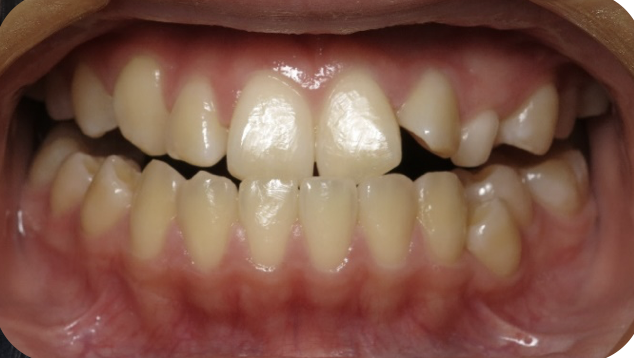

underbite corrected by expansion

Before

After